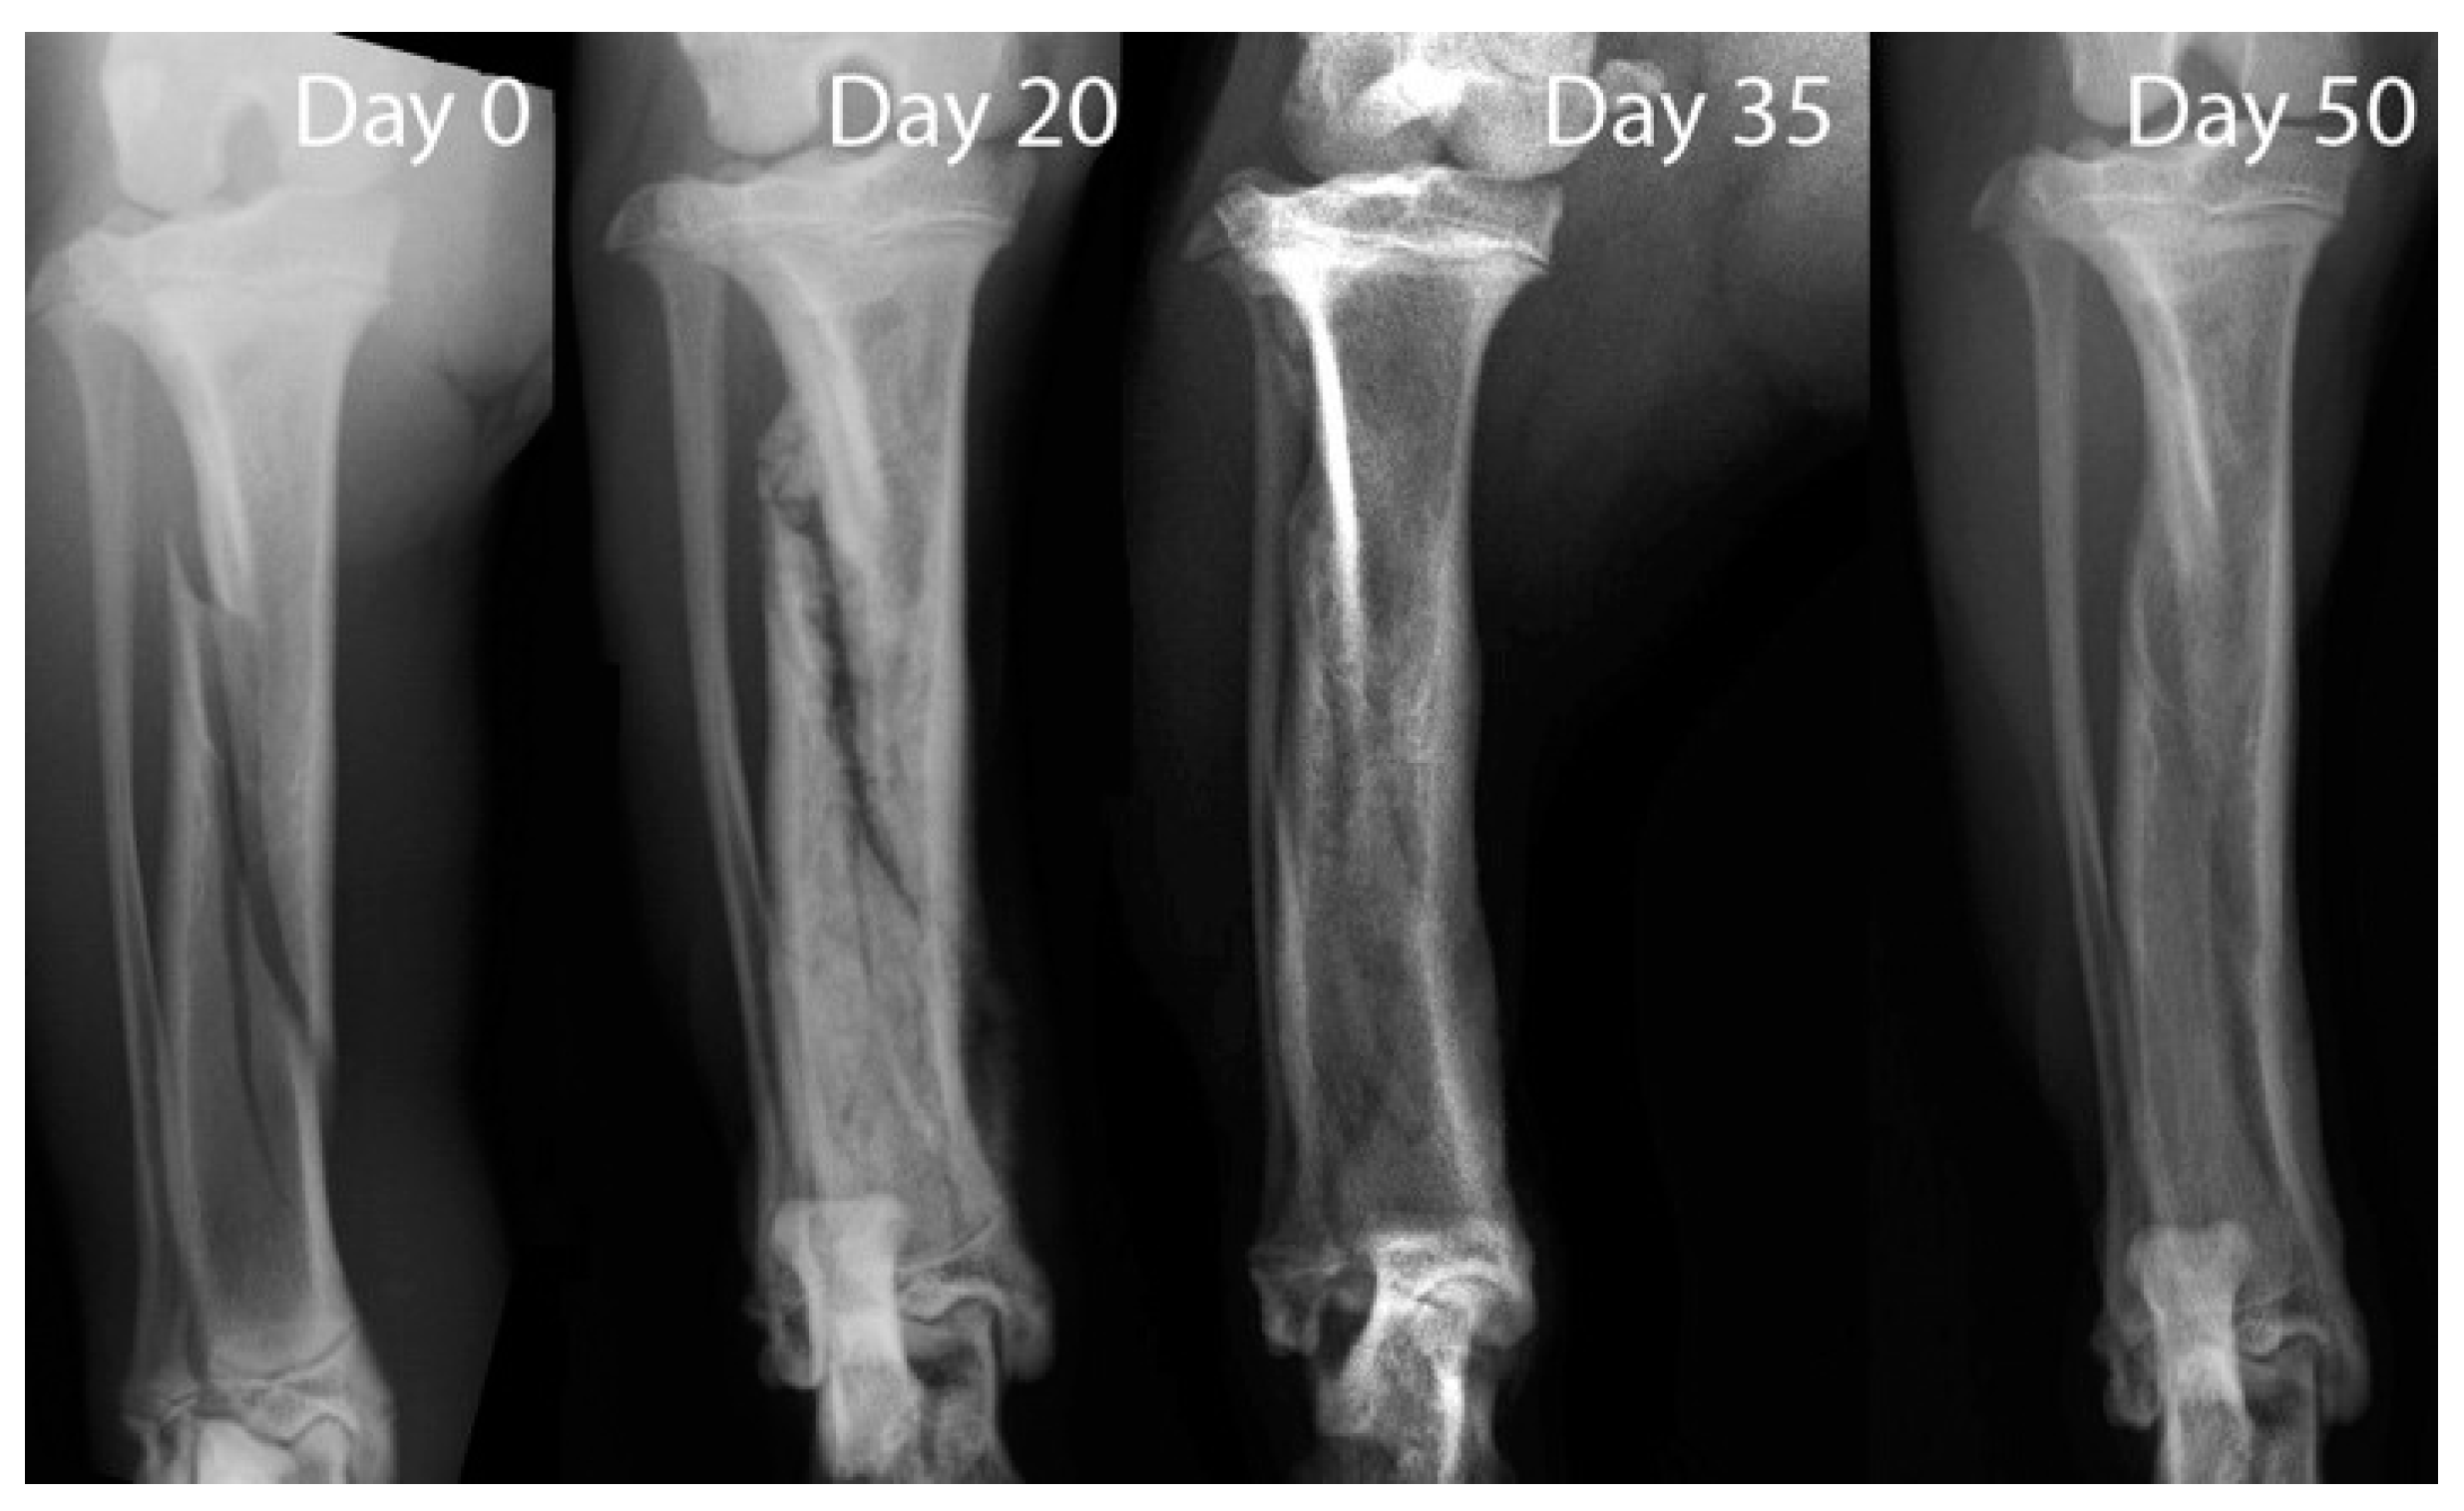

The radiographic study at T0 highlighted a tibial oblique non-displaced fracture; the fibula was intact. The X-ray exam at T20 showed irregular and blunted fracture margins due to the bone resorption. At T35 an early radiopaque callus with undulating and irregular contour was visible. The radiographic study at T50 showed an achieved complete osseous union of the fracture (Figure 1).

X-ray exam. The oblique fracture line of the tibial bone with intact fibula was visible on radiography at 0 day. Resorption of the fracture line was seen at day 20. At day 35, an early radiopaque callus was visible. Complete union of the fracture was obtained at day 50.